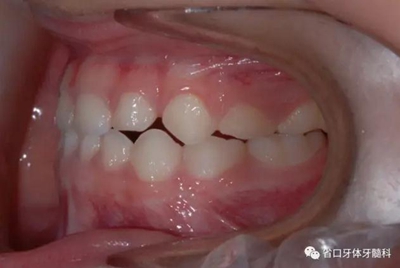

圖5 左側45度牙相

6.jpg

圖6 右側45度牙相